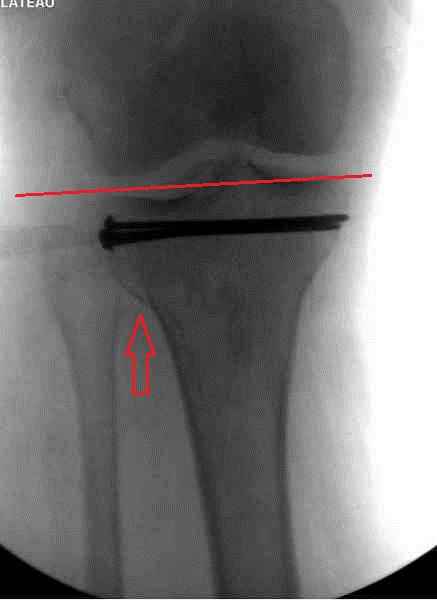

Снимки до и после закрытой репозиции

Пациентки прооперирована, результат чего на снимках. Выполнена открытая репозиция костей правой голени, синтез малоберцевой пластиной, б/берцевой винтами, имеющиеся фиксаторы не подходили, было принято решение репонировать отломки, синтез винтами, гипсовая повязка.

В данный момент локально отёк тыла стопы незначительный, двигательня функция сохранена, ограничена болевым синдромом. Пульсация артерий ослаблена, соответствует левой ноге. Рана - в области границы с пузырём область некроза 2.5*2 см, сухой, не увеличивается, под ним чувствительность сохранена. Чувствительность по всей поверхности кожи в норме, гипоестезия пальцев, при чём варьирует от нормальной, до почти анестезии в течении дня.

Мыщелок левой б/б кости репонирован закрыто, на контрольной рентгенограмме репозиция удовлетворительная, фиксировано спицами. гипсовая повязка.

Репозиция внутрисуставных переломов неудовлетворительная и не адекватна.

Сделайте снимок голеностопа контрлатеральной стороны, перенесите контур сустава на кальку и наложите её на свои послеоперационные Ргграммы - вам станет ясно что нужно сделать и какого стояния отломков достичь. Аналогичный

сценарий и для перелома наружного мыщелка б.б.- передний фрагмент стоит на месте, а задний не репонирован - в таком положении оставлять фрагменты нельзя, суставная поверхность должна быть реконструирована.

В лечении переломов пилона восстановление длины малоберцовой является индикатором и ориентиром для успешного лечения. Первый этап восстановления по длине не удался, малоберцовая остается короткой, и репозиция суставной поверхности осталась неудовлетворительной. Длина передней колонны не восстановлена, а в дистальном фрагменте имеется флексия. Оставлена без внимания потеря кости в метафизе. Шурупы 4.5 мм будут выступать после спадения отека, и возможно будут причиной мягкотканого осложнения в гипсе.